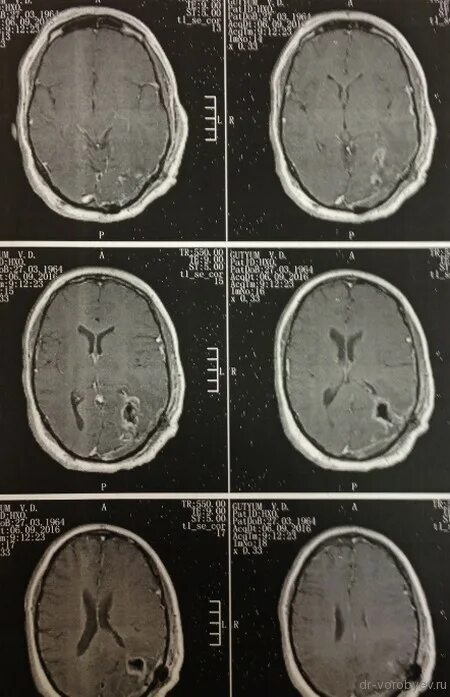

Астроцитома головного мозга прогноз после операции